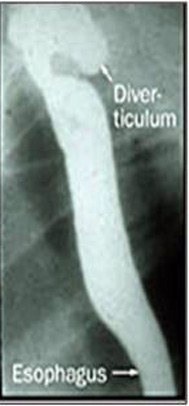

- צילום הוושט לאחר בליעת בריום והדגמת הסעיף בצוואר. התמונה האופיינית היא לאחר התרוקנות הבריום מהוושט נראה כיס עם בריום שנותר במקום הסעיף עקב הפרעות בהתרוקנות הסעיף (תצלום 4.1 ).

- אזופגוסקופיה (תצפית וושט) – בנוכחות סעיפים קטנים ניתן לראות חורים בדופן, המתאימים לפתחי הכניסה לסעיף. בנוכחות סעיף גדול האזופאגוסקופיה עלולה להיות מסוכנת, עקב האפשרות שהמכשיר יחדור לסעיף וינקב אותו.